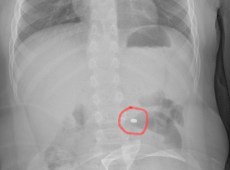

Il piccolo sta bene ed è tornato a casa a Gela

Bimbo di sei anni ingoia pila a bottone, salvato in sala operatoria

Un bimbo di sei anni ha ingerito una pila “a bottone” e così, dopo un primo controllo al pronto soccorso di Gela, è stato inviato all’ospedale Cannizzaro di Catania dove è stato operato per estrarre il corpo estraneo che avrebbe essere molto pericoloso